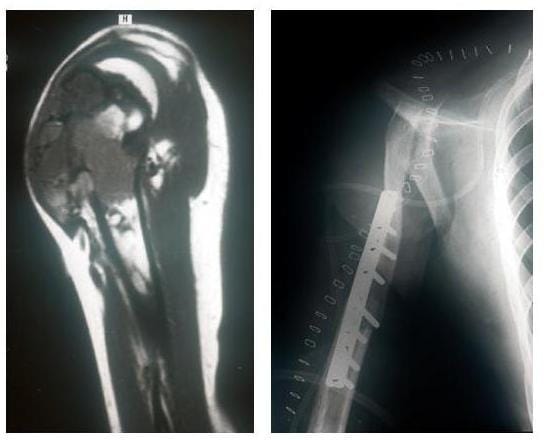

KLAVIKULA PRO HUMERO

Röntgenbilder eines bösartigen Knochentumors des Oberarms und Tumorentfernung und Ersatz durch das geschwenkte Schlüsselbein

Links: MRT-Bild eines bösartigen Knochentumors des Oberarms

Rechts: Tumorentfernung und Ersatz durch das geschwenkte Schlüsselbein

(Bilder: Orthopädie)